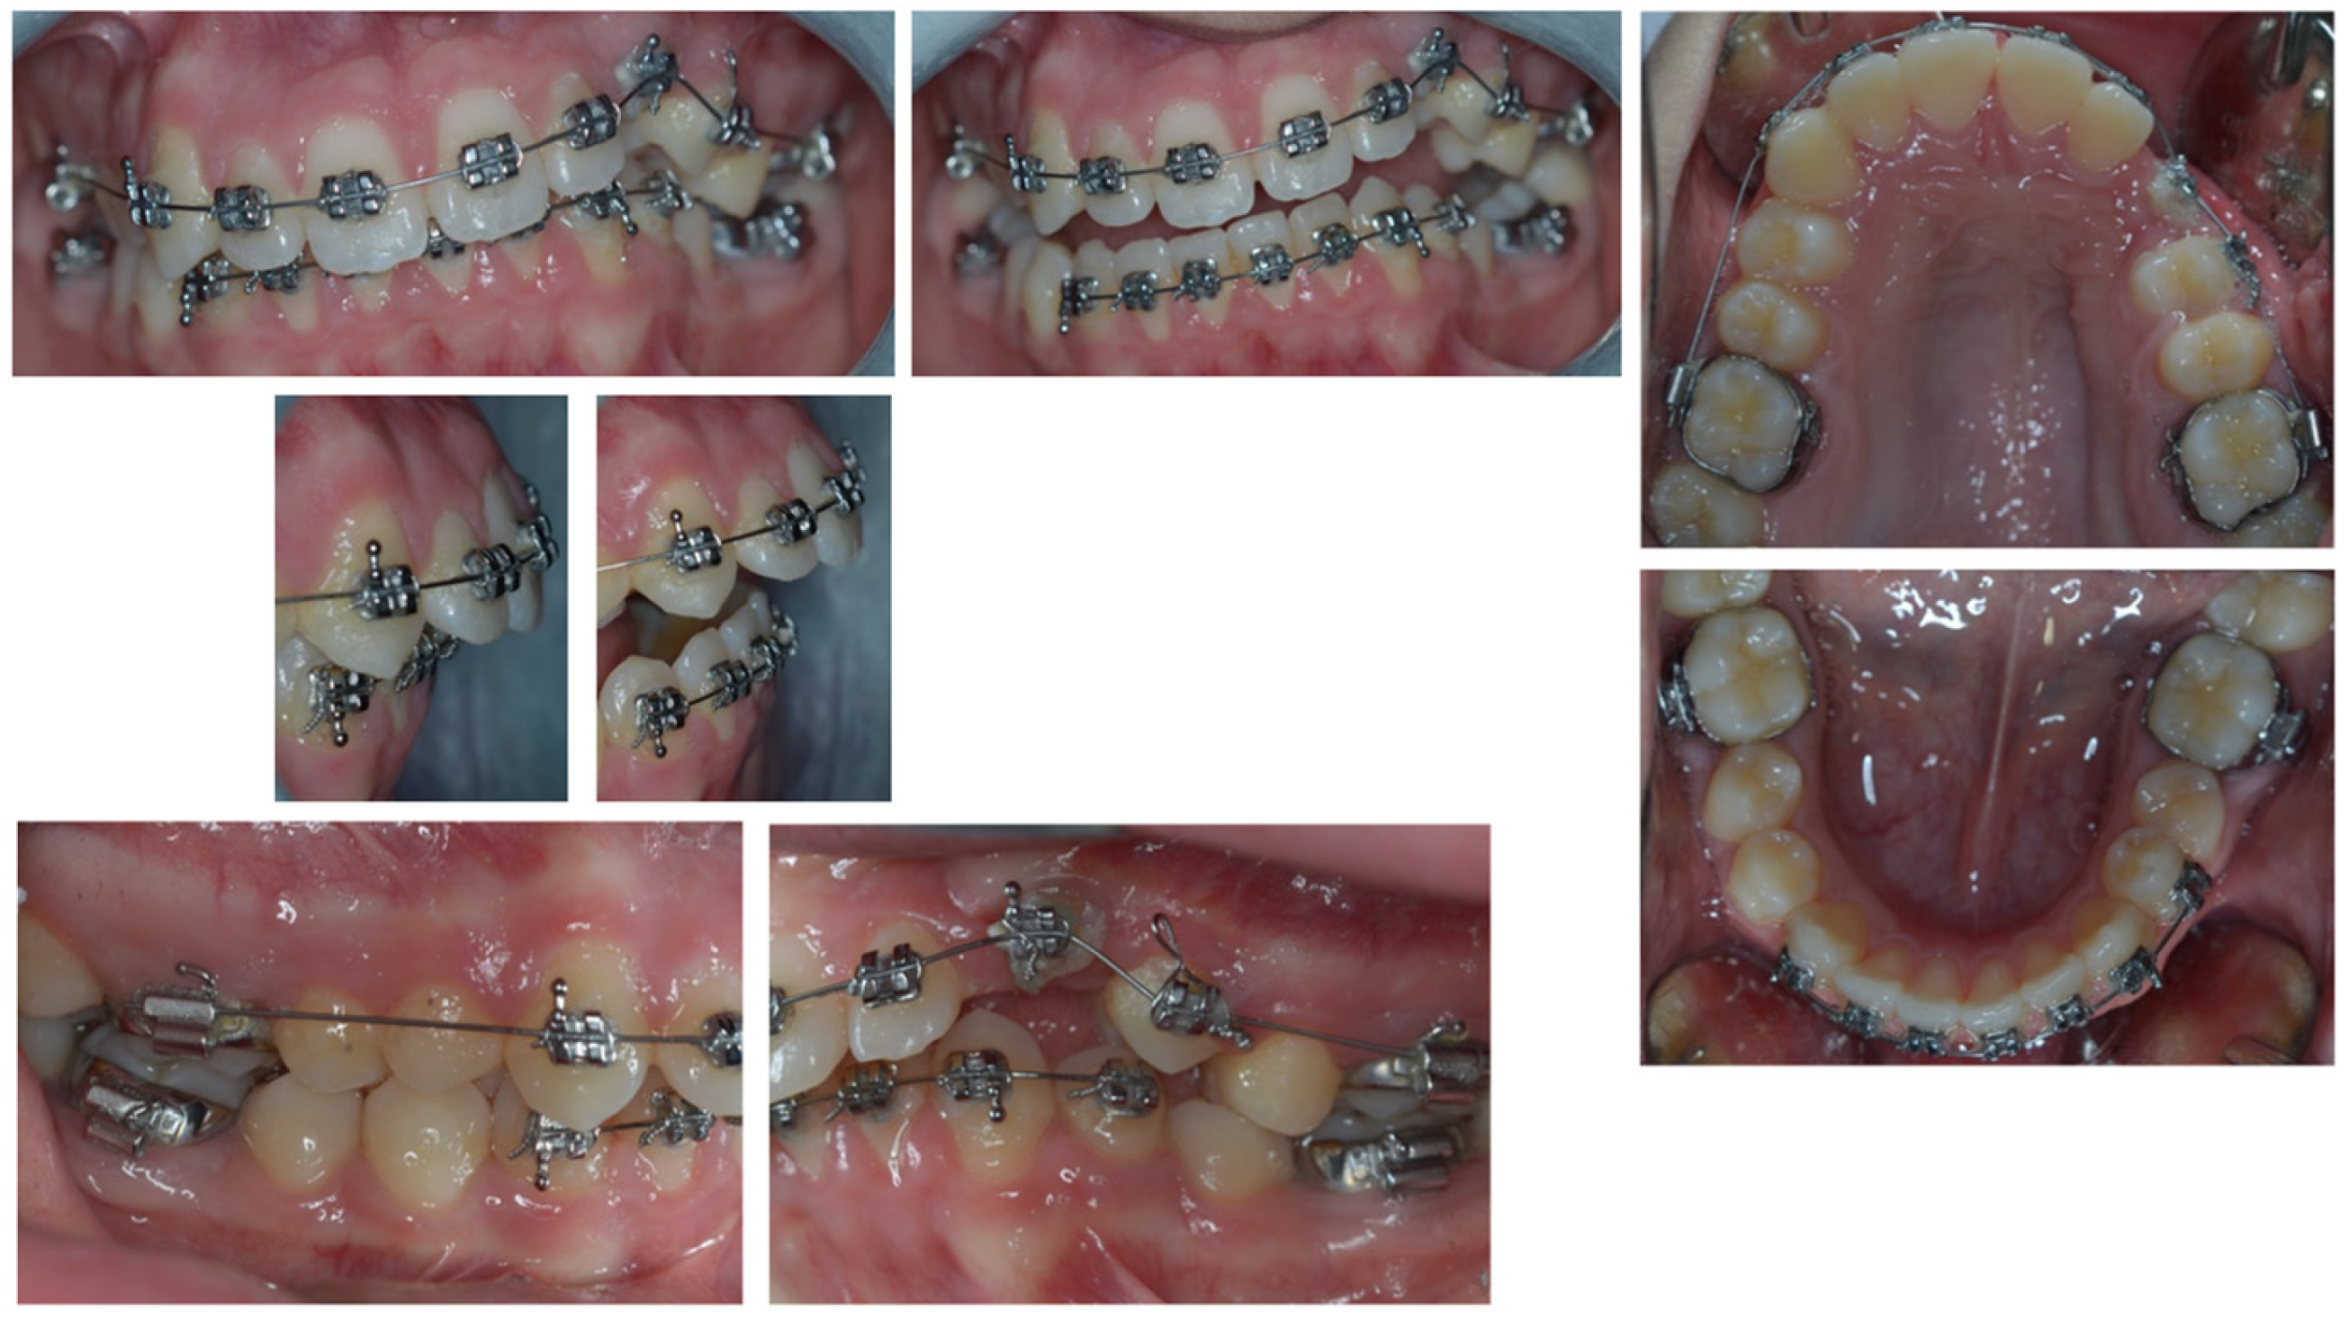

4. Follow-Up and Outcomes